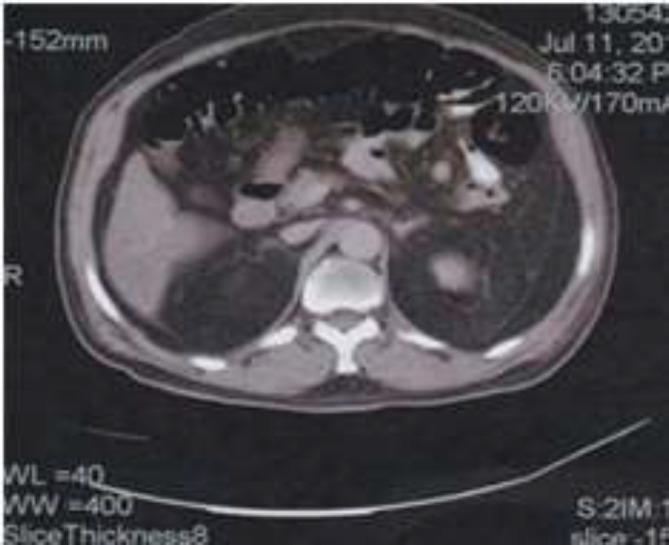

We report the case of a 57-year -old opium male addict, who was. Admitted for abdominal pain, nausea, and vomiting five days after off-pump coronary artery bypass surgery (OPCAB). An abdominal x-ray reported a colonic volvulus. Exploratory laparotomy showed acute abdomen resulting from a gangrene of long segment of splenic flexure caused by volvulus.

我们报告一例57岁男性阿片类药物成瘾者,在非体外循环冠状动脉搭桥手术(OPCAB)后5天因腹痛、恶心和呕吐入院。腹部X线检查报告为结肠扭转。剖腹探查显示为因扭转导致脾曲长段坏疽引起的急腹症。